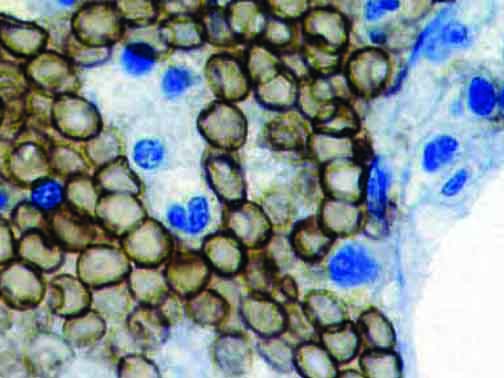

The first cytokines released are interleukin 1β (IL-1β) and tumor necrosis factor-α (TNF-α), which attract a variety of circulating white blood cells (WBCs) to the infection site, including neutrophils, monocytes, macrophages, and natural killer (NK) cells. This response, along with the antipathogenic chemicals released by these cells (i.e., complement), comprise the innate immune response. These cells directly attack the invading pathogen and also release additional cytokines, chief among them interleukin-1 and 6 (IL-6). IL-6 is essential for invoking the adaptive immune response, which calls T-cells, B-cells, and T helper (Th) cells to the infection site. IL-6 also stimulates further recruitment, proliferation and activation of macrophages.

It is the ICU physician who is most likely to witness one of the deadliest manifestations of the abnormal immunological response, the cytokine storm syndrome (CSS). This response is also referred to by some as the cytokine release syndrome (CRS). CSS is characterized by continuous activation and expansion of macrophage and lymphocyte populations, which secrete large amounts of cytokines, causing the cytokine storm. This massive cytokine release is akin to hemophagocytic lymphohistiocytosis (HLH) disease, a syndrome characterized by initial unchecked and persistent activation of cytotoxic T lymphocytes and NK cells.

Clinical and laboratory manifestations of HLH include fever, enlarged liver and/or spleen, neurologic dysfunction, coagulopathy, liver dysfunction, cytopenias (i.e., low levels of erythrocytes, leukocytes, and/or platelets), hypertriglyceridemia, hyperferritinemia, hemophagocytosis, and eventually diminished NK cell activity as the immune system becomes progressively paralyzed. HLH can be familial (primary HLH) or secondary to another disease process (sHLH), such as rheumatic disease, in which it is referred to as macrophage activation syndrome (MAS, characterized by elevated ferritin).